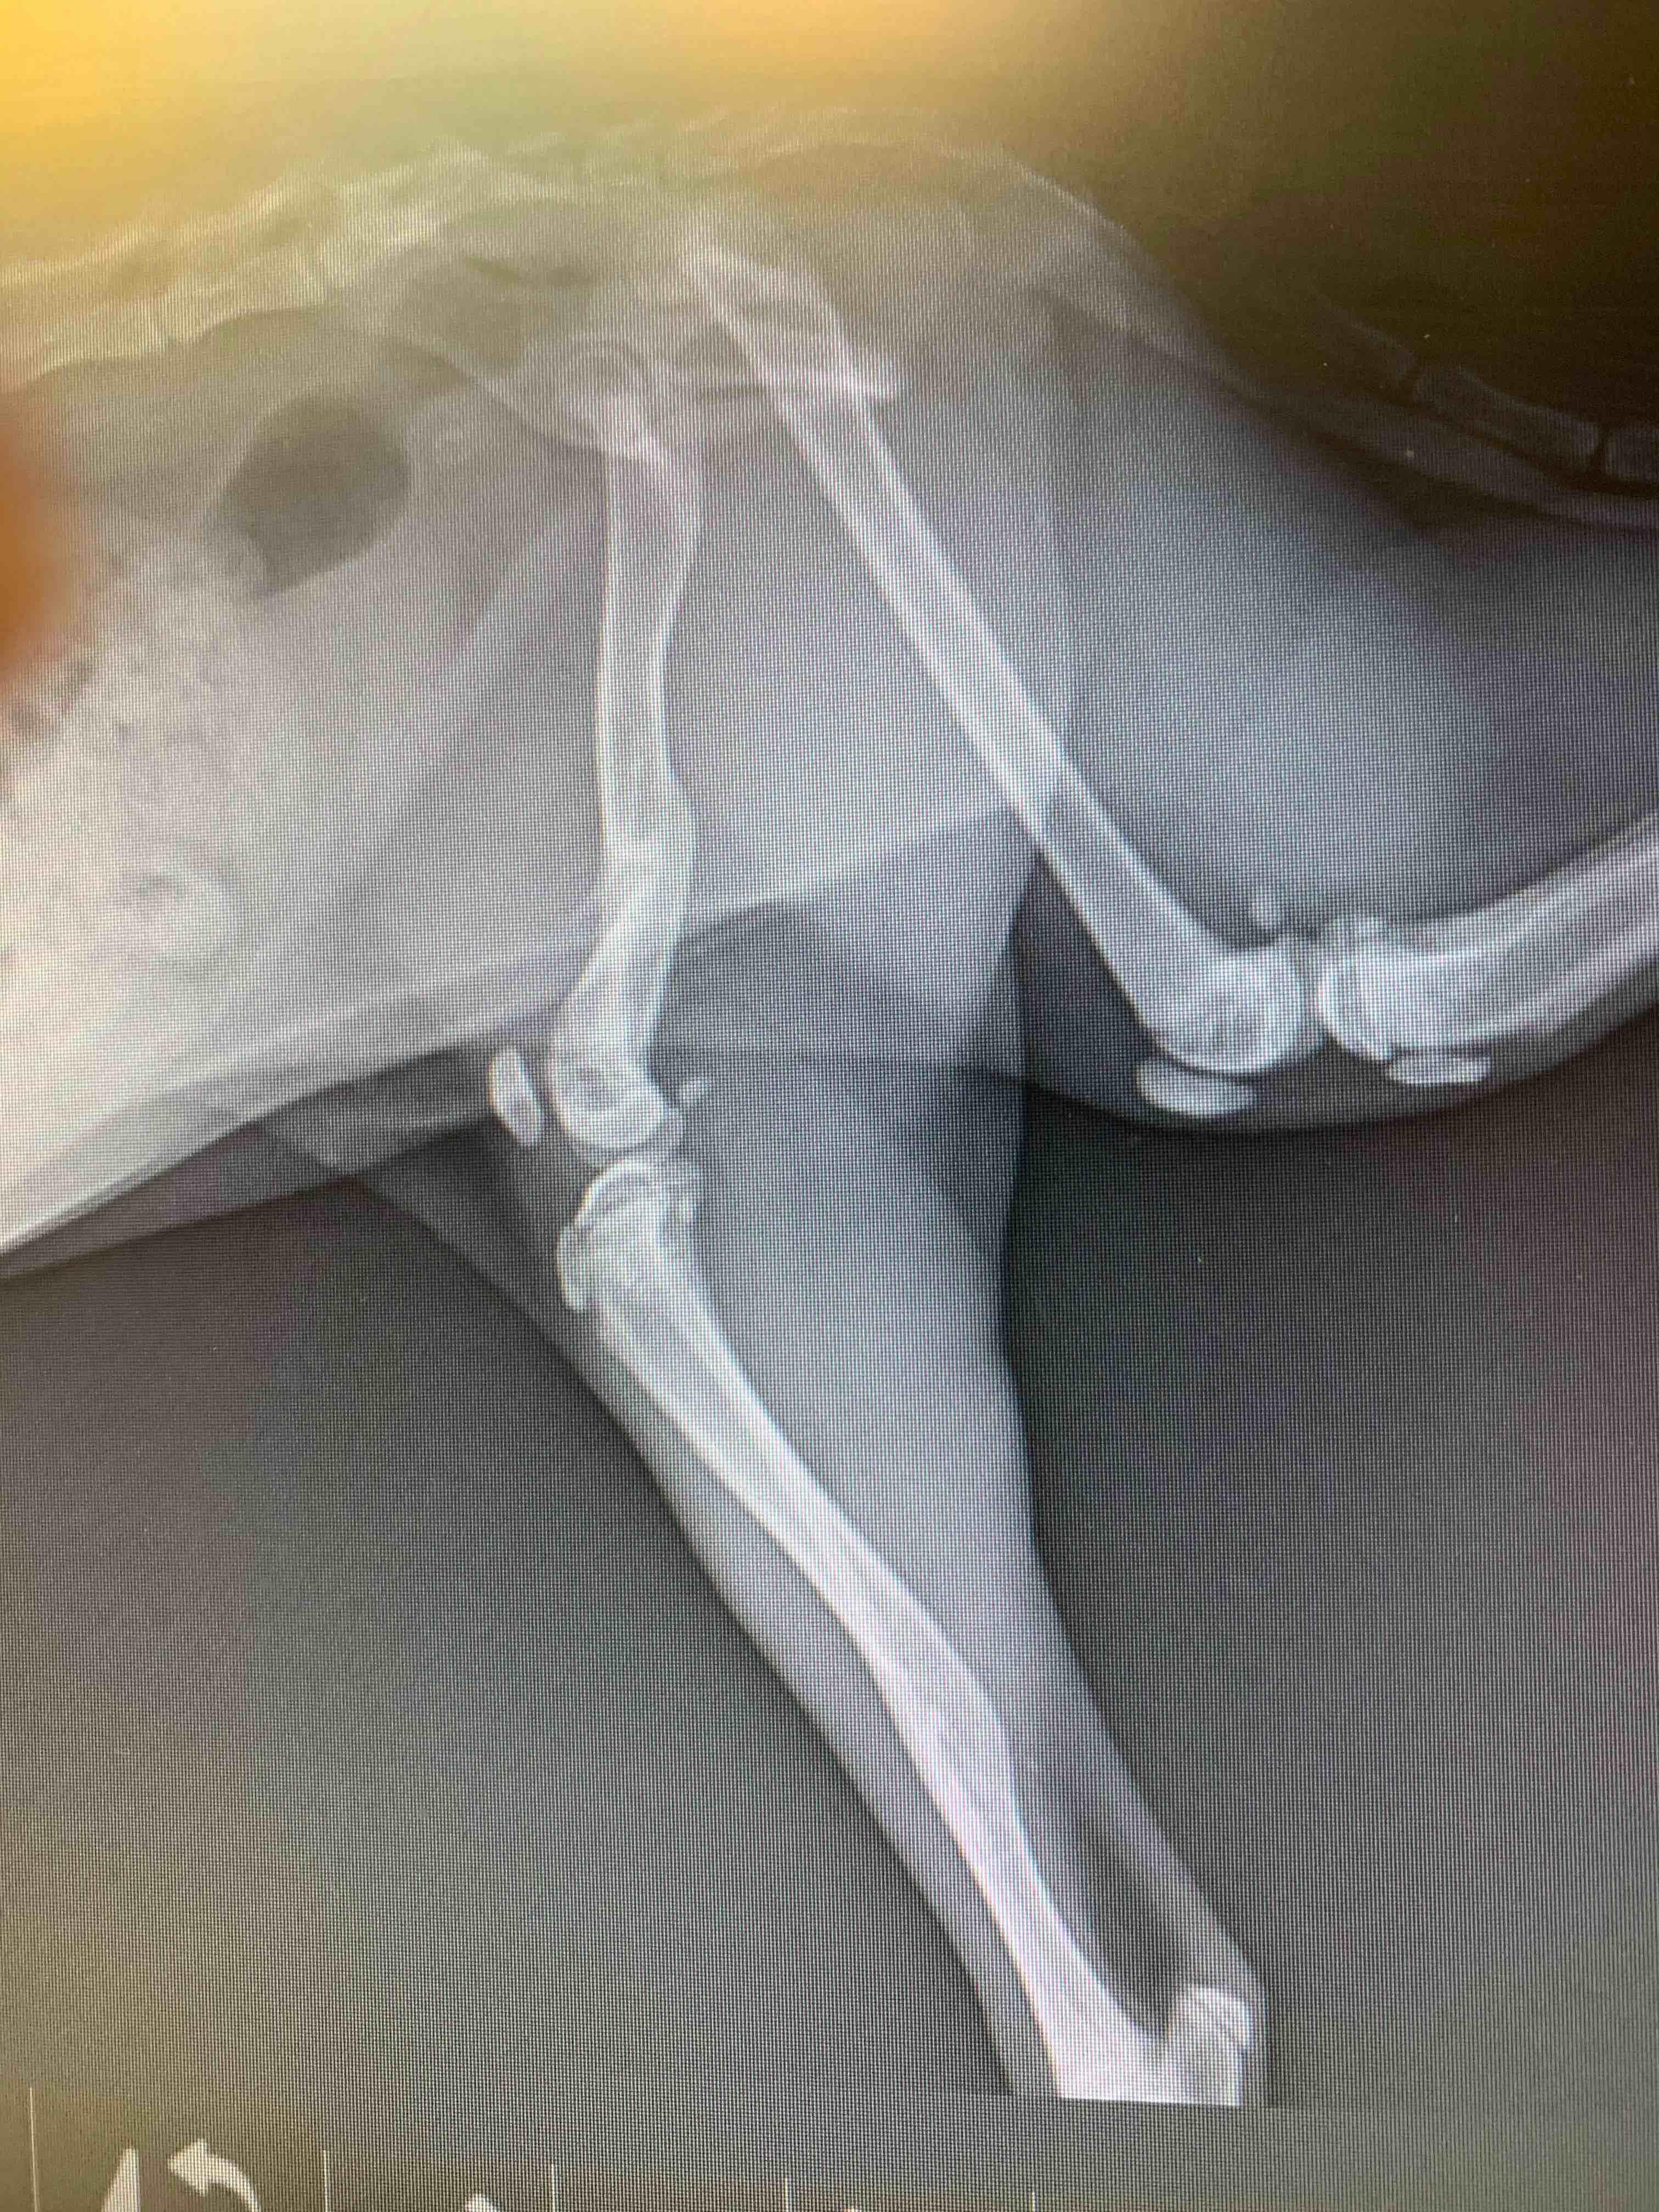

Her tibia & femur were fractured in May. She appeared to heal well until Oct 6. Now she limps a little, sits/lays with leg at odd angles, falls off of laps & furniture, cries out if picked up wrong, has reduced overall play a bit, keeps it still during play, uses it very lightly when jumping/running. Sometimes, she acts like nothing’s wrong. X-rays show misaligned knee, dislocated hip, badly healed femur. Vet #1 says amputate, #2 says no bc she’s using it. Amputate now while she’s small/young?

I think a third option might be available based on the x-ray - an FHO procedure to remove the ball of the femur and allow for more comfort with the dislocated hip. To me it sounds like Maggie is not using her leg much at all, and the vets don't think an FHO would help (which is certainly possible, I'm just suggesting based on what I can see in the x-ray) it sounds to me like amputation might be best. I would worry that she cries out because the leg is sometimes painful.